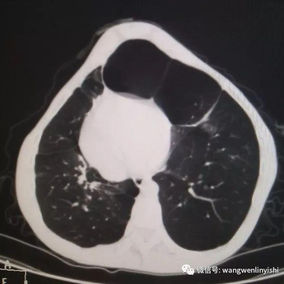

After a preoperative examination, it is observed that the patient's anterior chest wall protruded severely, reaching its peak at the xiphoid process, which presented as a 90-degree angle when viewed from the side. The heart is displaced to the right chest cavity, and the torso is severely deformed, characterized by a broad chest and a noticeably narrowed waist and abdominal area. The narrowing is most pronounced above the pelvis. Moreover, a chest CT scan reveals two large cysts located between the heart and the anterior chest wall in the lower lobe of the left lung, measuring 7x8 cm and 9x10 cm respectively.